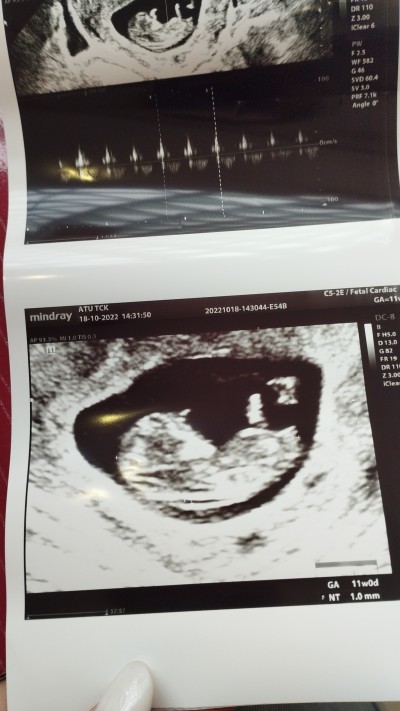

Resimli usm cinsiyyet

Her kese merhaba. Ben bu gun usm oldum. Cinsiyyət de bana 80% kiz dediler. Ancaq gender testinde erkek cikmisti. Resim koyucam. Erkek bebek cinsiyyət organi gorenler var mi?

11.6

Ben gördüm ama haftan çok küçük belli olmaz şimdi bence canım ya

Bende gördüm cnm Allah gönlüne göre versin

Hayır net 3 çizgi var bence kesin kız